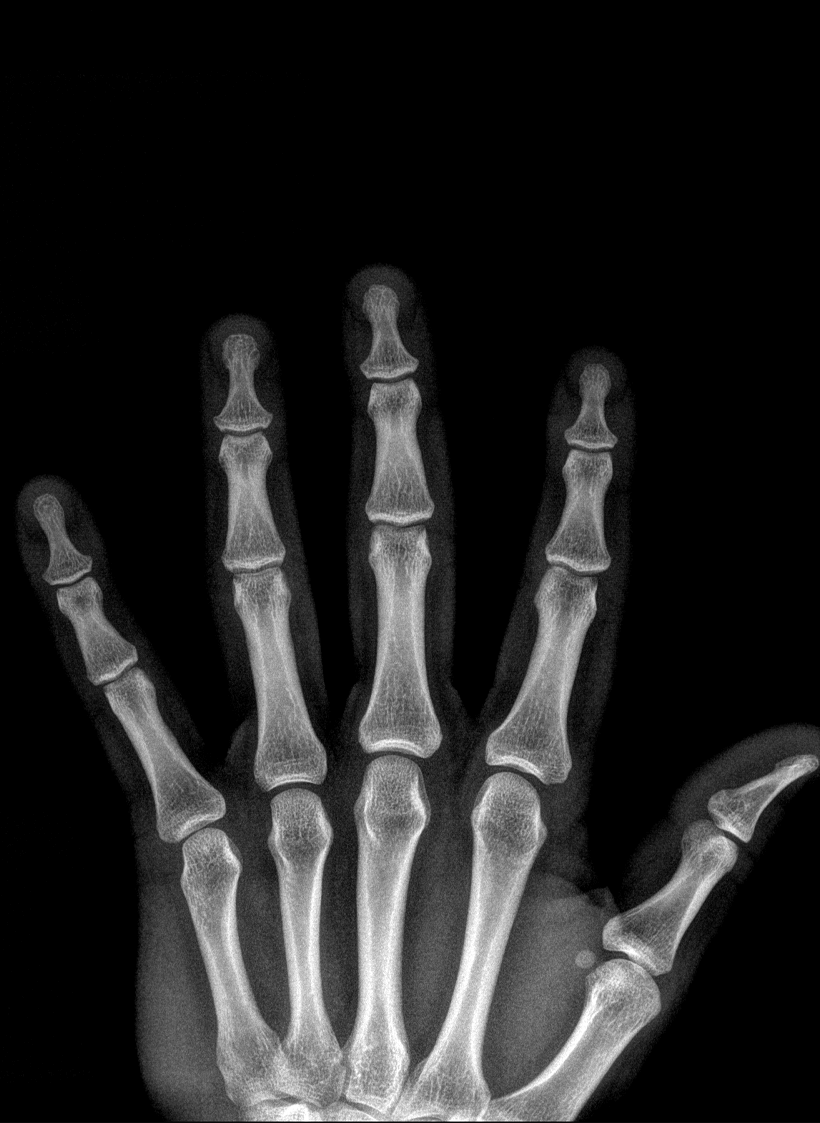

Seit meiner Ausbildung widme ich mich in meiner Arbeit und Forschung intensiv der Handchirurgie. Somit kann ich Ihnen das gesamte Spektrum der konservativen und operativen Behandlung von Hand- und Unterarmerkrankungen anbieten. Als Unfallchirurg habe ich mich auf die Versorgung von handnahen Verletzungen spezialisiert. Als Orthopäde widme ich mich der Versorgung von abnützungsbedingten Erkrankungen der Gelenke sowie Sehnen- und Nervenerkrankungen.